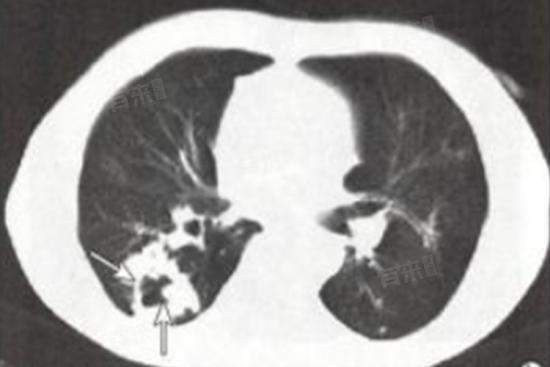

- 肺有空洞是指肺组织中出现空腔,是一种常见的肺部疾病表现,可以由多种原因引起,主要包括结核病、肺脓肿、肺癌等。

- 结核病由结核杆菌引起的传染病,结核菌侵入肺部后,会引起肺组织发炎,进而形成空洞。肺脓肿由细菌感染引起的肺部炎症,严重时会导致肺组织坏死并形成空洞。肺癌细胞生长迅速,会破坏肺组织,从而形成空洞。但并非所有肺癌都会导致空洞形成,且空洞型肺癌只是肺癌的一种类型。

- 如果影像学检查发现肺有空洞,需要通过进一步的检查明确其性质,CT引导下肺穿刺活检,通过CT引导下的穿刺技术获取肺组织样本,进行病理学检查明确诊断。痰细胞学检查可以寻找癌细胞,支气管镜检查直接观察支气管内部情况,并获取组织样本进行病理学检查。